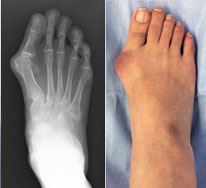

外反母趾とは 足の親指の付け根が変形をし、クの字に曲がってきて、 第一中足骨に痛みが伴ったり、靴が当たり痛くて、歩けなかったりする症状です。 昔は、年配の女性の病気のように思われていましがたが、 今は、男性や若年化してきて、老若男女問わずして、悩んでいる人がとても多くなっています。 私も、今まで気にもしたことが無かったのですが、 最近、右足が特に、外反母趾??て思って、いろいろ調べていました。 すると、いろいろな事がわかってきました。  ...